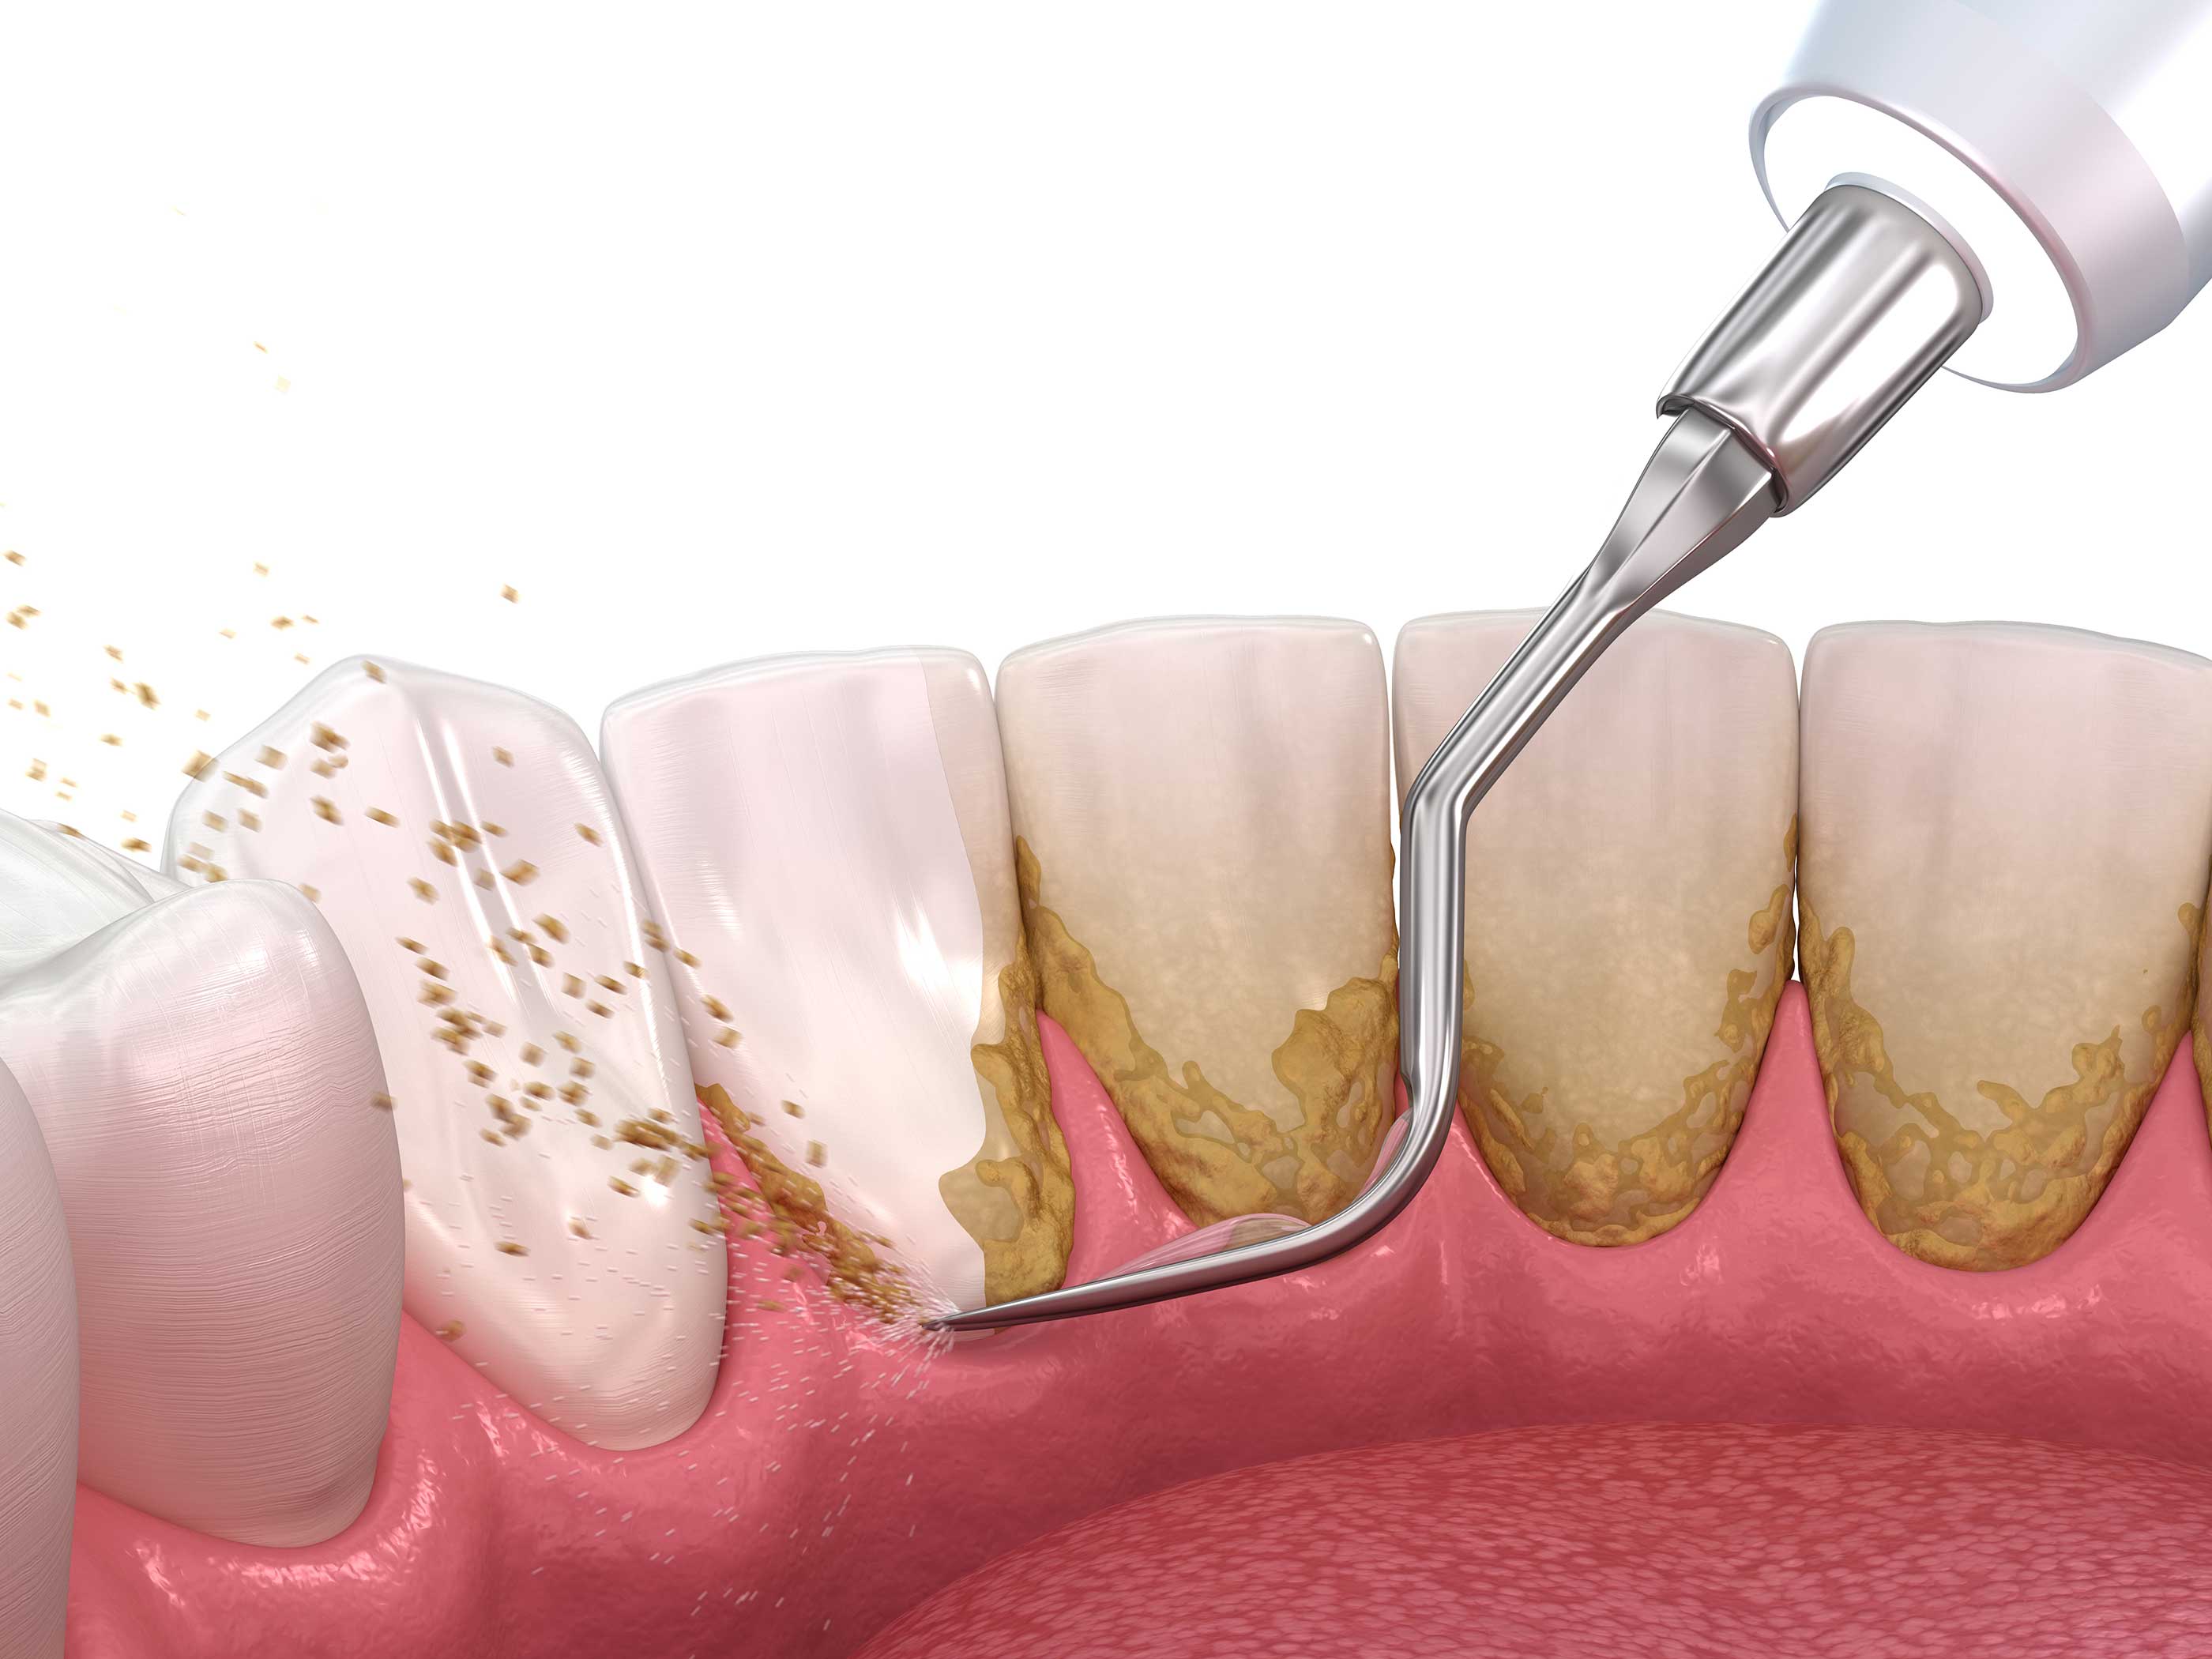

Uklanjanje zubnog kamenca i naslaga je ključna preventiva za zdravlje zuba i desni. Profesionalno čišćenje uklanja tvrde naslage i plak, smanjuje rizik od upala desni i karijesa, te održava prirodan izgled i dugotrajnost zuba.

Redovni stomatološki pregledi omogućavaju pravovremeno otkrivanje problema i planiranje adekvatne terapije. Preventivne procedure, uključujući fluoridaciju i edukaciju o higijeni, pomažu u očuvanju zdravih zuba i desni, sprečavajući ozbiljnije intervencije i čuvajući prirodan izgled osmeha.